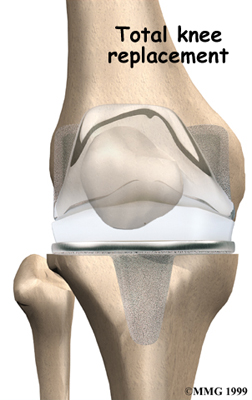

Artificial Knee Replacement

An artificial knee replacement is the ultimate solution for advanced knee OA.

Surgeons prefer not to put a new knee joint in patients younger than 60. This is because younger patients are generally more active and might put too much stress on the joint, causing it to loosen or even crack. A revision surgery to replace a damaged prosthesis is harder to do, has more possible complications, and is usually less successful than a first-time joint replacement surgery.

Related Document: FYZICAL Peachtree Corners Guide to Artificial Joint Replacement of the Knee